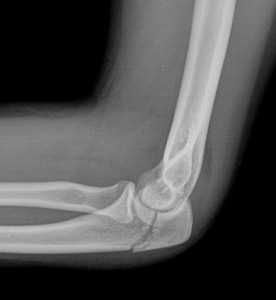

(Слева) На снимке определяется чрезмыщелковый перелом плечевой кости у женщины 63 лет после падения на выпрямленную руку. Линия перелома пересекает оба мыщелка, но не переходит на суставную поверхность. Имеется незначительное медиальное смещение дистального отломка, что является частой находкой при таких травмах.

(Справа) На фронтальной компьютерной томограмме с реформатированием без контрастирования у этой же пациентки подтверждается чрезмыщелковый ход перелома и отчетливо видно медиальное смещение дистального отломка. Кроме того, данные КТ подтверждают сохранность суставной поверхности плечевой кости.